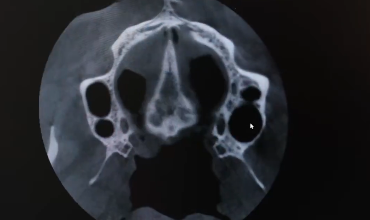

Ankara İl Sağlık Müdürlüğü, modern diş hekimliğinde tanı ve tedavi süreçlerini ileri bir seviyeye taşımak amacıyla 75. Yıl Ağız ve Diş Sağlığı Hastanesi’ne Diş Bilgisayarlı Tomografi (CBCT) cihazı kazandırdı. Yeni cihaz sayesinde hastalarda yüksek çözünürlükte üç boyutlu görüntüleme yapılabiliyor.

Hastanede hizmete giren konik ışınlı bilgisayarlı tomografi, ağız, çene ve yüz bölgesinin üç boyutlu olarak görüntülenmesini sağlıyor.

Yeni nesil Diş BT cihazı, dental implant planlaması, ortodontik değerlendirmeler, çene eklemi (TME) rahatsızlıkları, kök kanallarının tespiti, gömülü dişlerin tanısı, kemik patolojilerinin değerlendirilmesi ve çene-yüz travmalarının analizi gibi birçok alanda kullanılabiliyor.